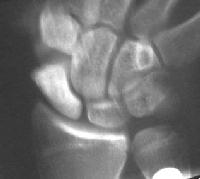

Clinical Example: Scaphoid fracture with total avascular necrosis similar to Preiser's disease

One of the problems with scaphoid fractures is ischemia of the proximal fracture fragment resulting in delayed union, nonunion or irretrievable avascular necrosis. In this case, ischemic changes involving the entire scaphoid are documented following a scaphoid fracture due to minimal trauma. This progressed with cystic changes and AVN on MRI. The patient had persistent pronounced wrist stiffness and pain. As pointed out to me by Dr. Lawrence Schneider (thanks!), this is technically not true Preiser's, for the fracture preceded the AVN.